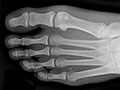

Los huesos o las articulaciones podrían mostrar señales de daño a causa de una enfermedad, como osteoporosis, artritis reumatoide, osteoartritis, gota o enfermedad de Paget. Vea imágenes de artritis reumatoide en los pies y artritis reumatoide en las manos.